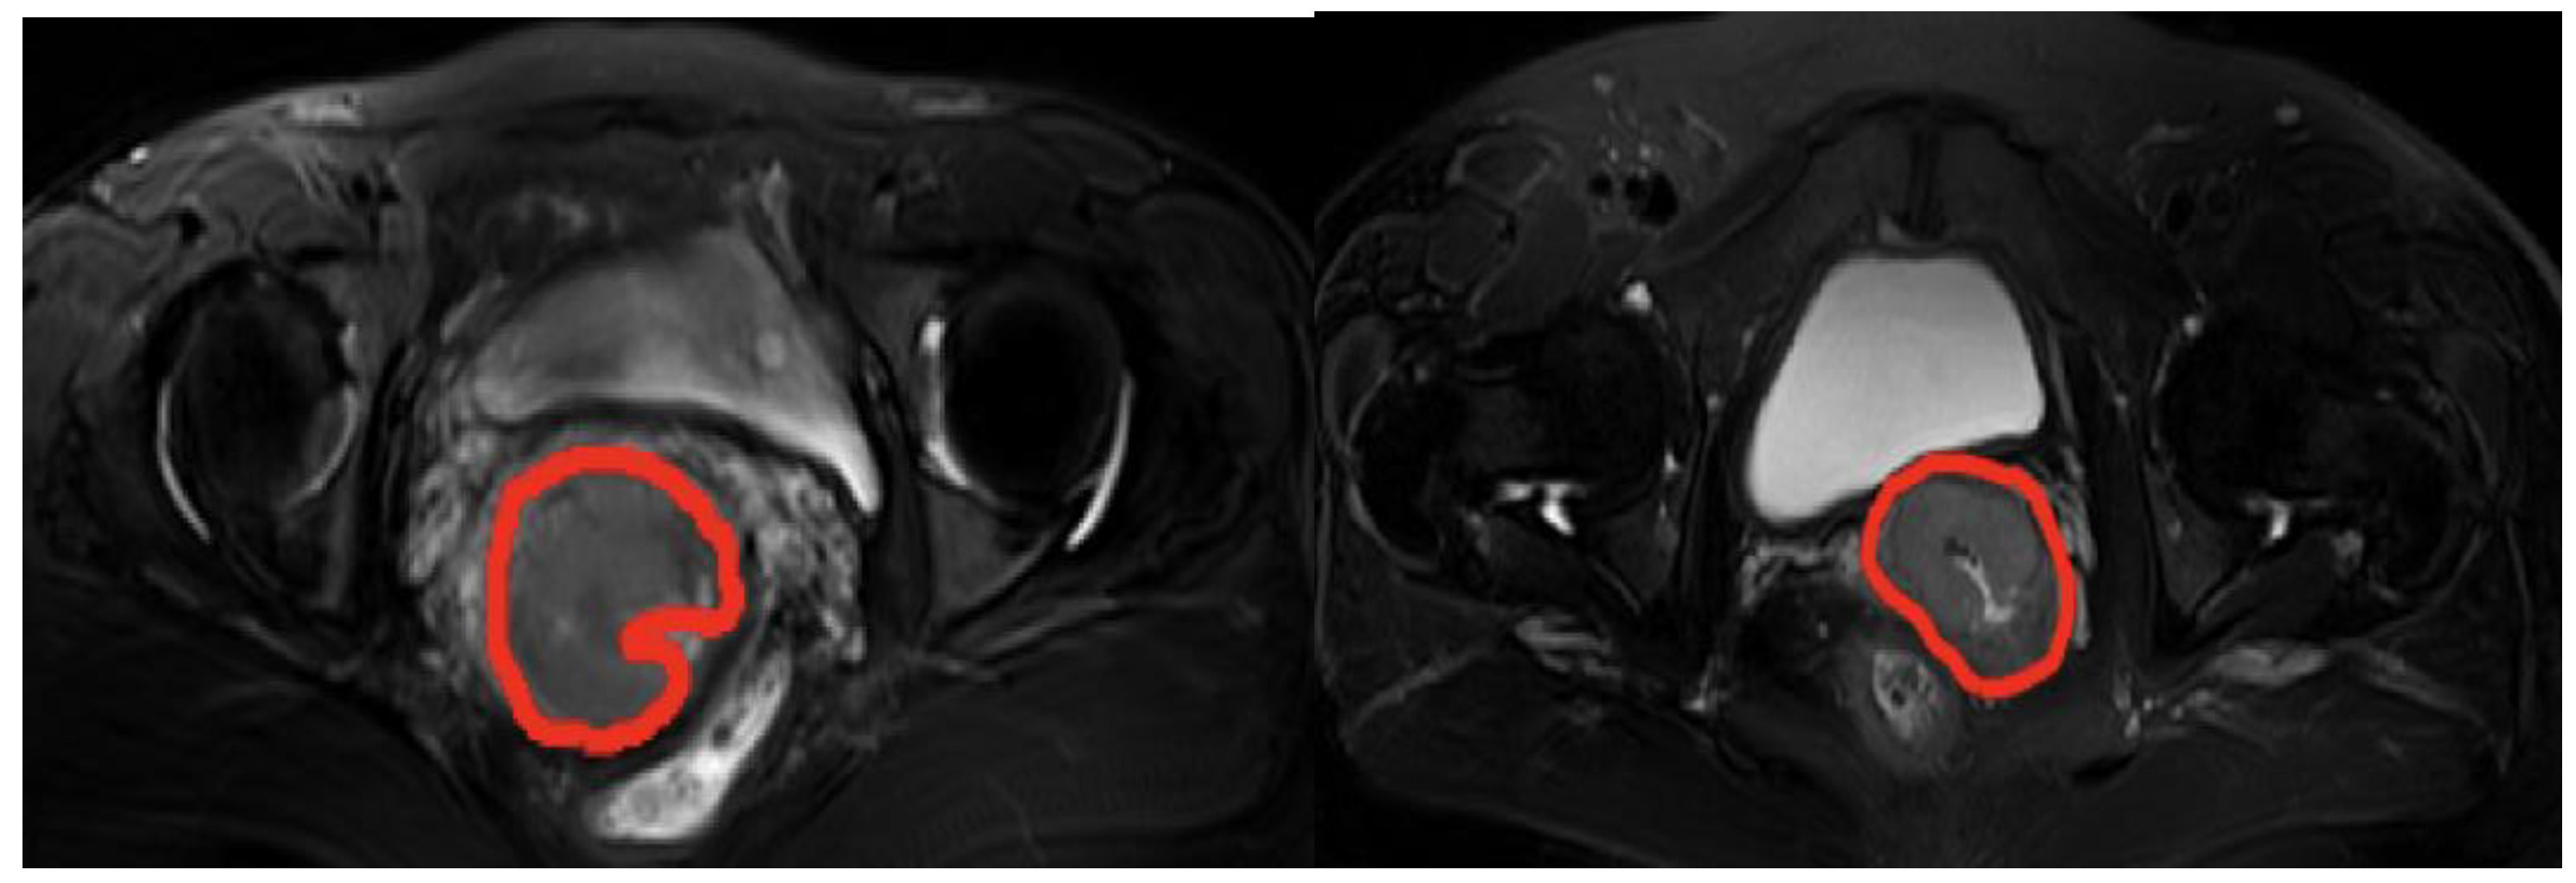

2.2.2. Data Preprocessing

2.2.3. Extraction of Domain-Specific Features

2.2.4. Extraction of Abstract Features